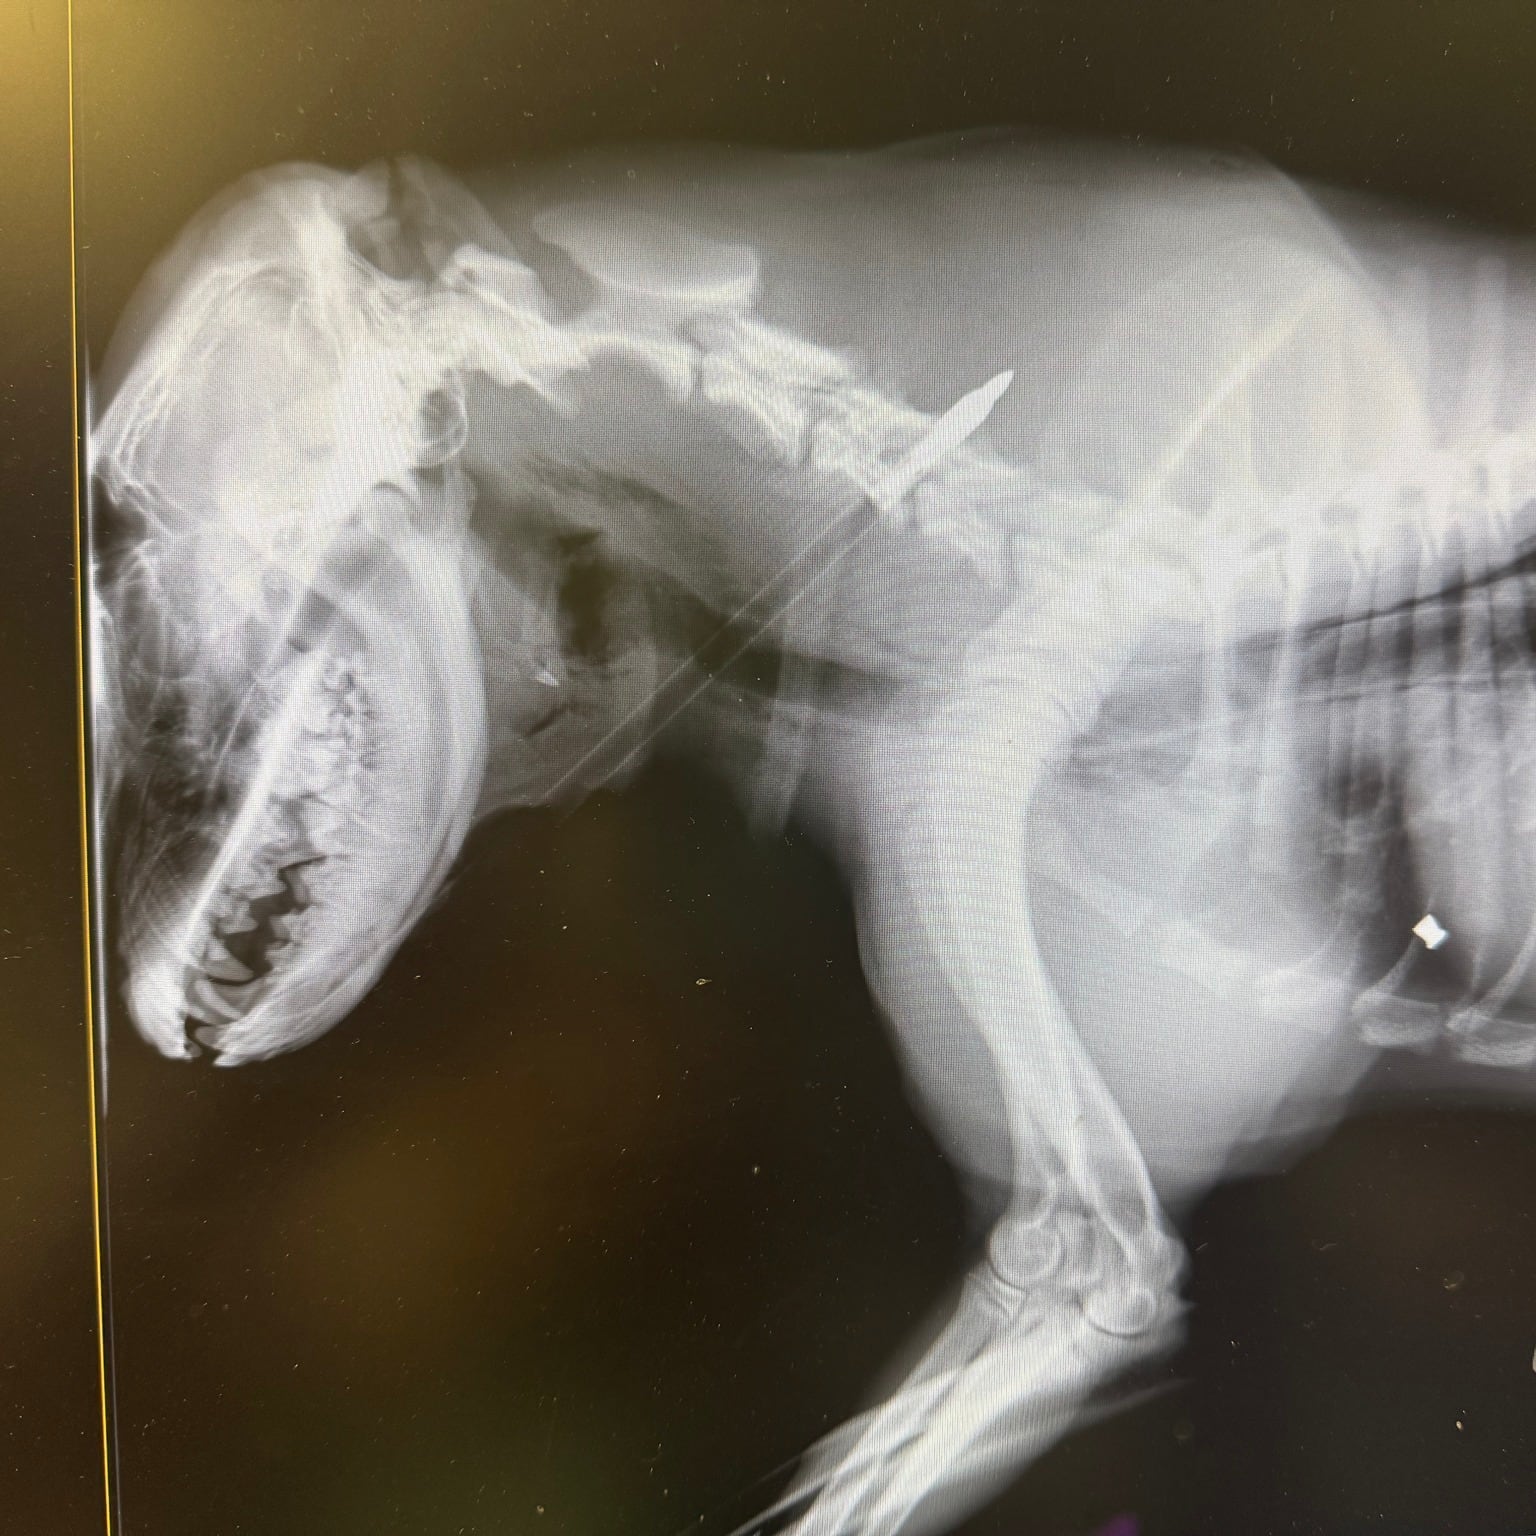

Lo acomodaron en un recinto especialmente preparado para él. Y, una vez que le realizaron las radiografías, los médicos y voluntarios pudieron ver claramente que la flecha lo había atravesado y había quedado encajada cerca de su columna vertebral y esófago. Como si eso no hubiera sido suficientemente horrible, también tenía una bala alojada en el abdomen. “Evidentemente alguien quería muerto al perro”, dijeron desde Stray Rescue of St. Louis, que rescata a animales abandonados, golpeados, heridos, aterrorizados, derrotados y traicionados.

Mientras preparaban al perro para entrar al quirófano, nuevos estudios evidenciaron que la flecha estaba perforando la tráquea. No sería fácil de extraer y necesitaba un especialista capacitado para hacer la operación. “Lo aseguramos en la camilla y lo arropamos con mantas y una almohada para mostrarle que no todos los seres humanos son monstruos. Despedimos a Lucky Charm (como lo bautizamos) con mucho cariño y muchos besos. Fue muy duro, pero era su única oportunidad y se merecía todo nuestro esfuerzo”.

La cirugía duró cuatro difíciles horas en las que los especialistas trabajaron para remover la flecha que había perforado la tráquea y el esófago. Afortunadamente, no había producido daño en la columna vertebral. “Los cirujanos dijeron que Lucky Charm había salido muy bien de la operación y que ¡había desayunado como un campeón! Aunque todavía no estaba fuera de peligro y esas 24 horas siguientes serían críticas, todo indicaba que en unos días, el perro podría salir de la internación”.